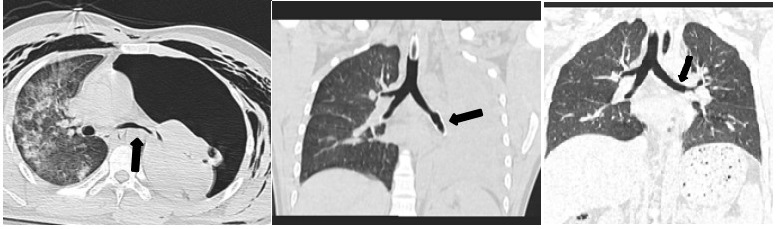

气管支架治疗5例:CT或气管镜明确诊断为软骨环破裂和(或)软化致气管塌陷后,经气管镜置入金属或硅酮支架。1例左主支气管塌陷,置入金属支架1枚,18 d后取出,但管壁仍软化塌陷、脱机困难,予置入Y形硅酮支架,1年后拔出(图 1 A~C),恢复良好。1例隆突上方气管及左主支气管广泛软骨环形破裂、憩室形成,右主支气管开口处软化、塌陷狭窄,置入金属支架1枚,3周后取出(图 2 A~C),恢复良好。1例因左侧气胸、左主支气管塌陷,置入金属支架1枚,术后出现左肺不张,多次经气管镜吸痰治疗,术后2周取出,左肺复张(图 3 A~C)。另2例气管塌陷患者,各置入金属支架1枚,2~3周后取出。5例患者置入支架后均观察到粘痰堵塞,每日予气管镜吸出。5例患者均效果良好,未见支架移位,支架取出后随访6个月以上,未出现气道狭窄。

| A 为右主支气管狭窄术前;B 为金属支架植入术后2 d;C 为支架植入术后16 d 图 2 右主支气管损伤置入金属支架1例 |